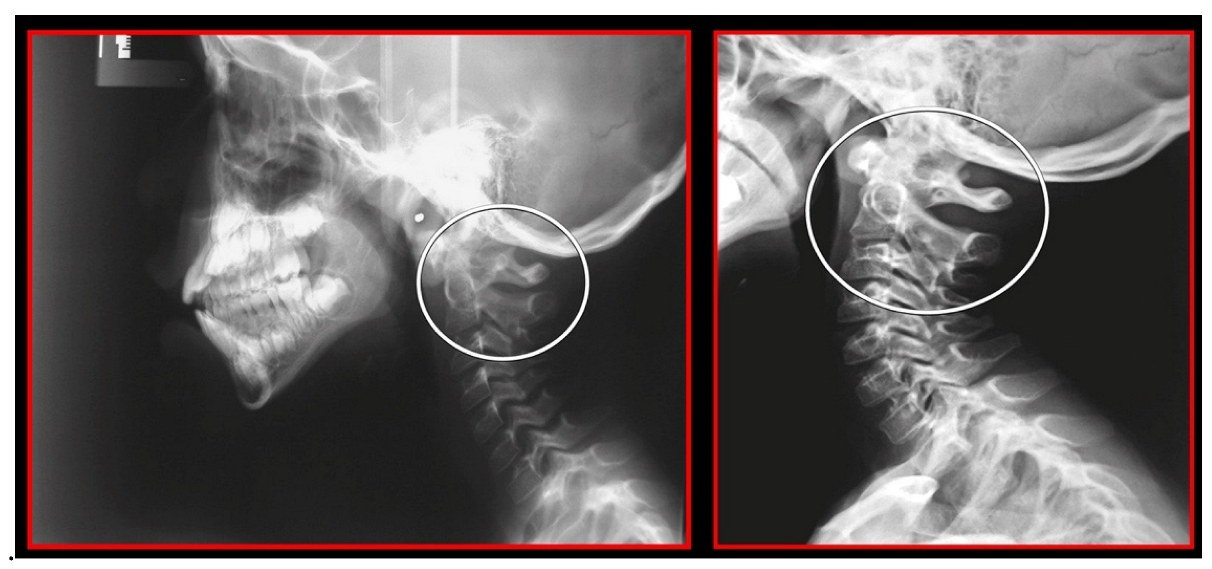

7.3. Ponticulus Posticus Syndrome

- Rocabado, M.; Gutierrez, R.; Gutierrez, M.F.; Gutierrez, M.J. Case report: Anterior open bite correction treatment by dental treatment and physical therapy through craniocervical mandibular and occlusal stabilization. Cranio 2021, 10, 1–6. [Google Scholar] [CrossRef]